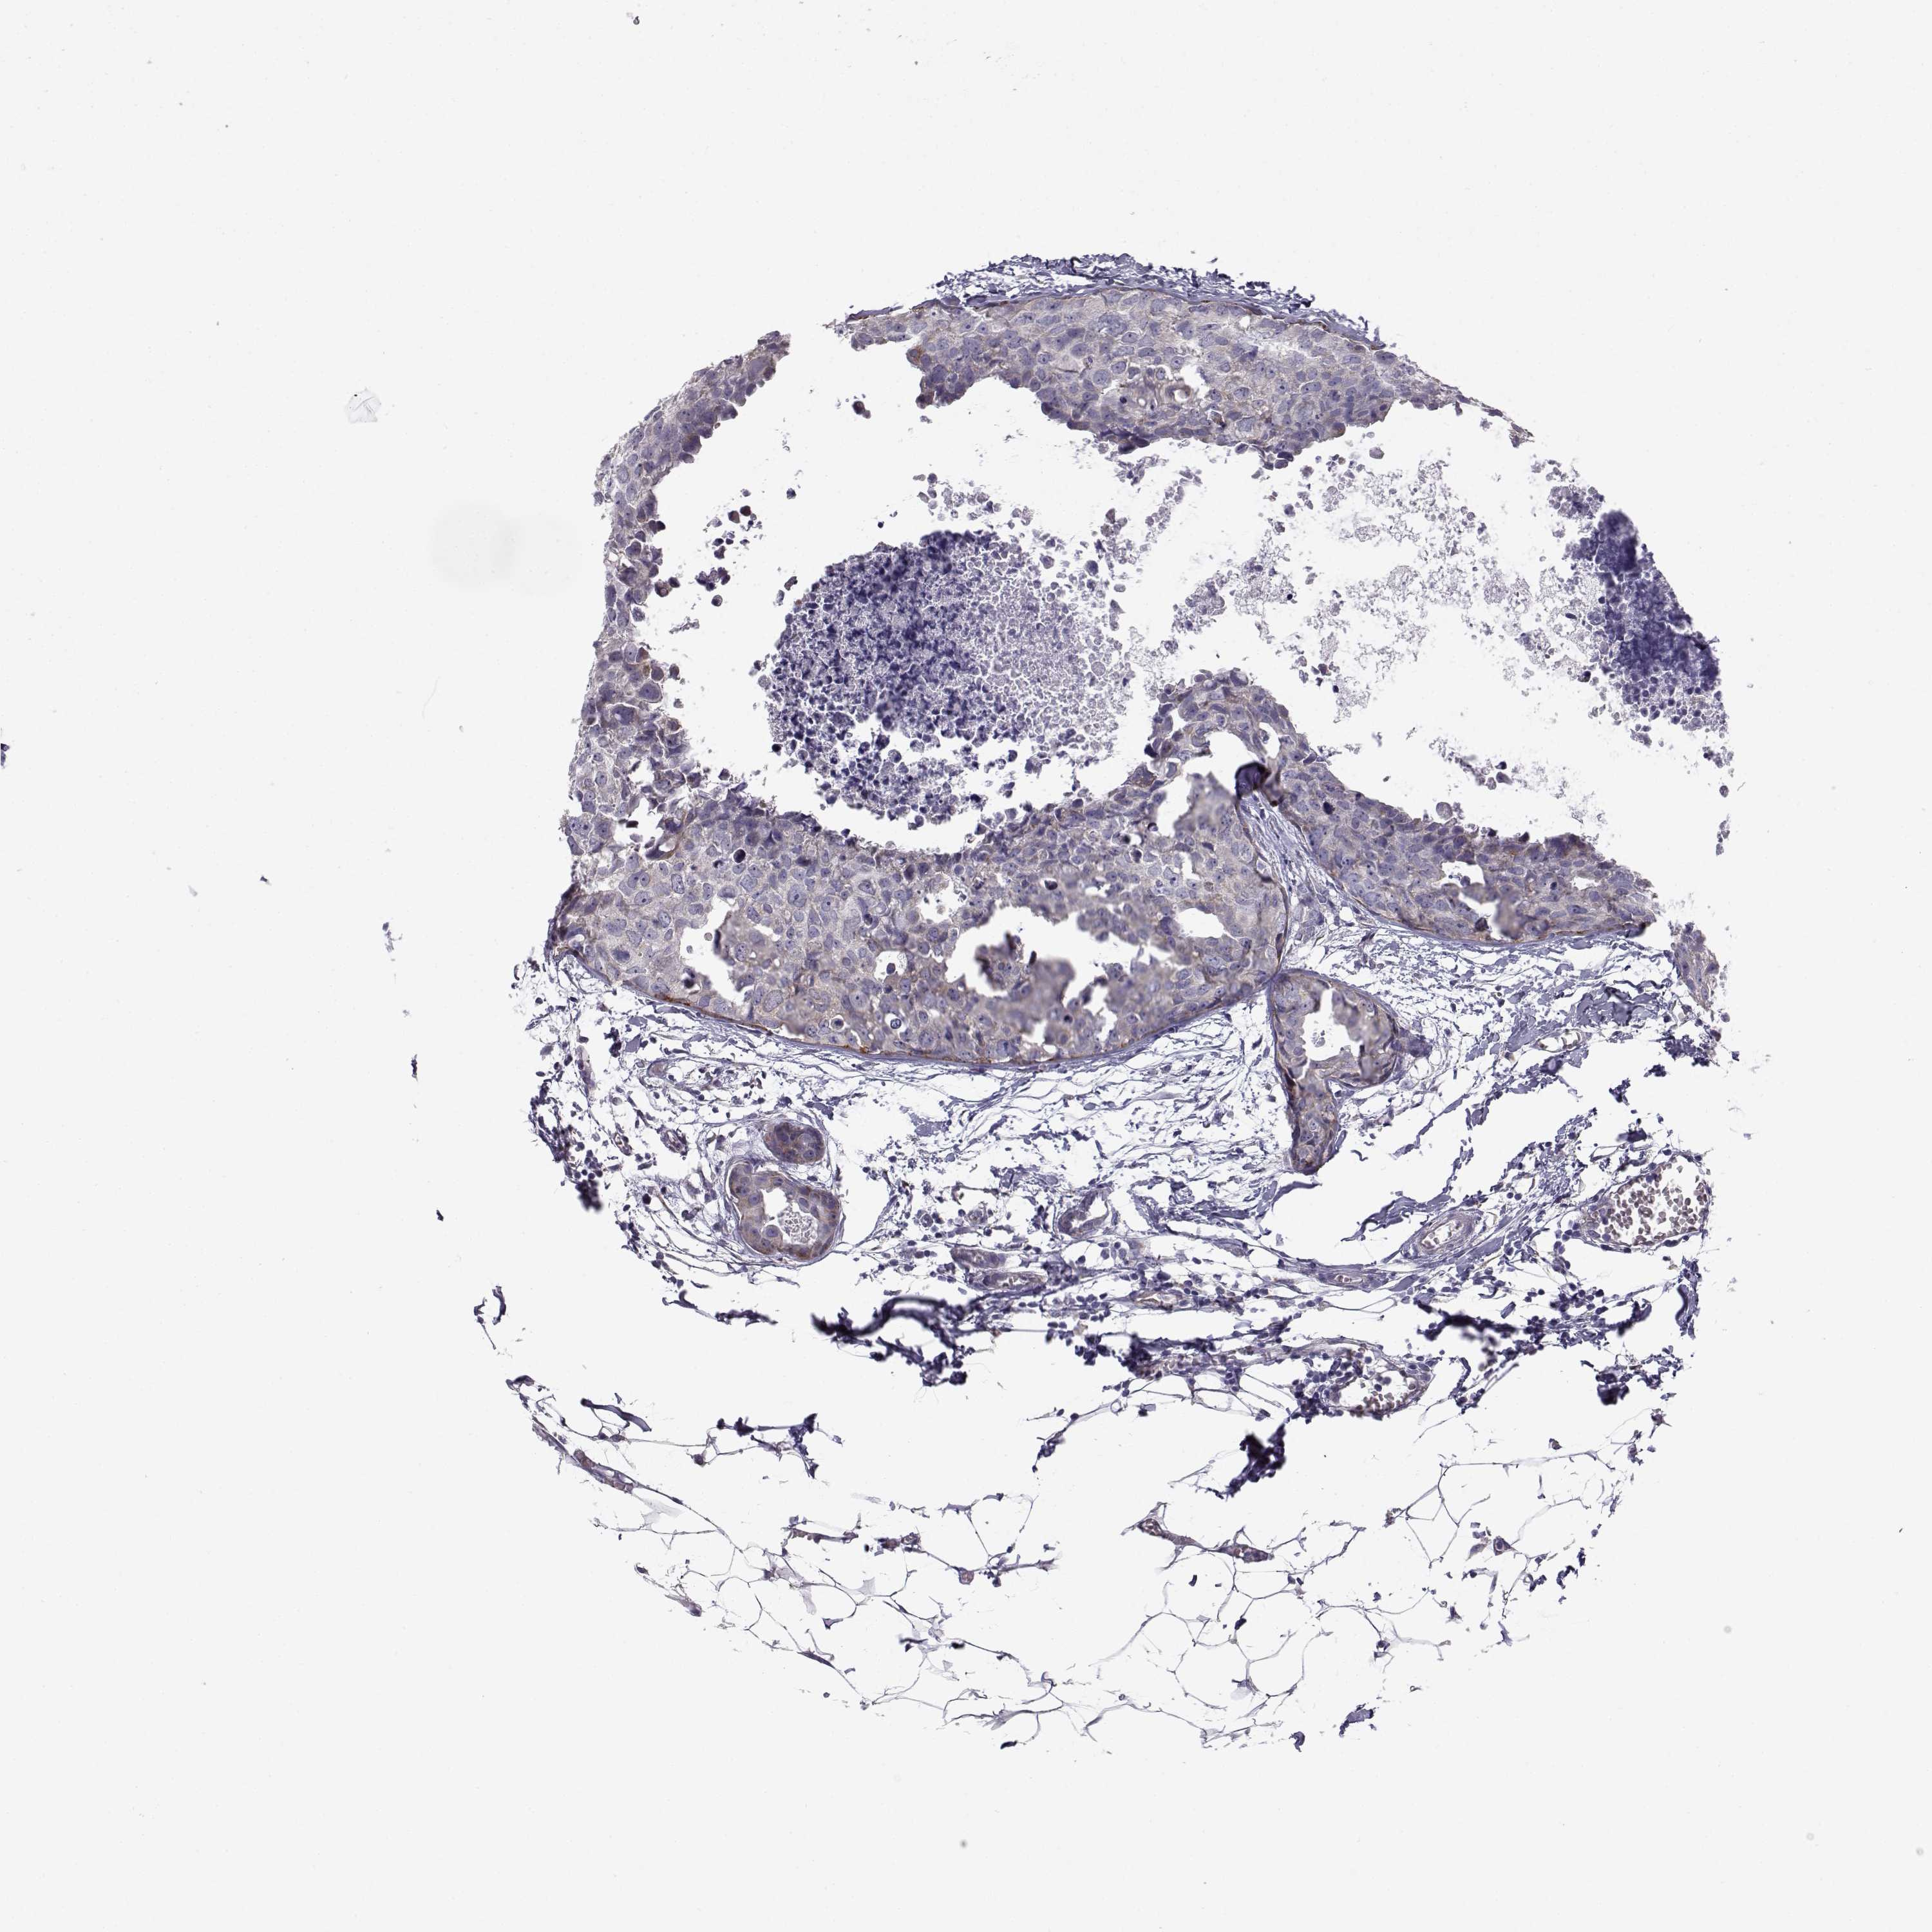

BRCA TCGA BRCA VALIDATION PROTEIN EXPRESSION

Breast cancer

Human cancer